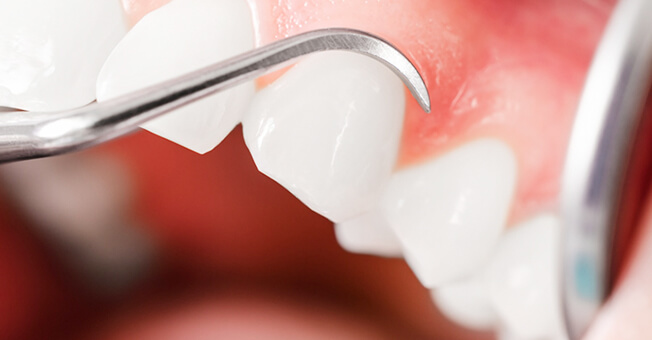

審美歯周病治療

見た目も美しく

歯周病治療を行うと歯茎が下がったとよく聞きます。残念ながら、炎症が長期に渡り存在していた歯茎や、重度歯周病では、治療を行うことにより歯茎が下がり炎症が除去されると歯茎が下がってしましやすいです。そういった場合、セラミックス治療を行うことで審美的に改善を図ることがあります。

また、歯周病はないのに、歯茎が下がってしまうことによる審美性が損なわれてしまう病気があります。そのような場合、歯茎の移植などを行うことにより、歯を削ることなく審美性を改善させることができます。 -